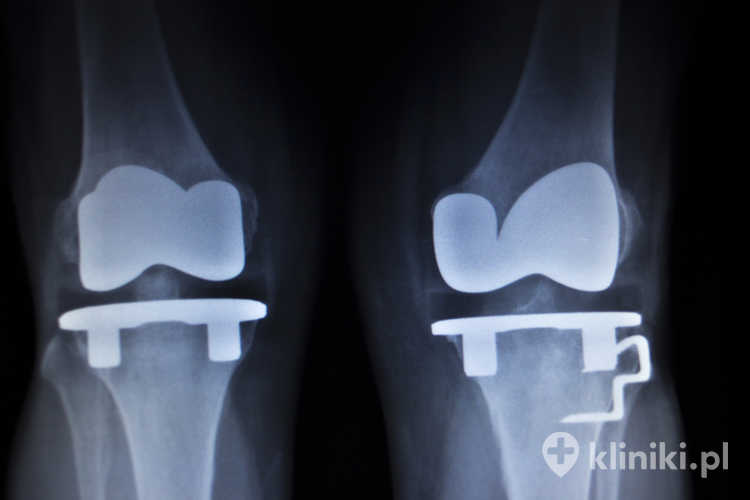

Przy pomocy endoprotezy kolana leczy się następstwa ciężkich urazów, takich jak złamania śródstawowe lub rozległe uszkodzenia chrząstki

Dzięki poprawie wyników leczenia, stosowaniu coraz nowszych materiałów, z których wykonuje się endoprotezy, oraz coraz dokładniejszej wiedzy na temat właściwości mechanicznych kolana, zabieg endoprotezoplastyki stawu kolanowego jest coraz szerzej i z powodzeniem stosowany w praktyce klinicznej. Zgodnie z danymi amerykańskimi corocznie przeprowadza się około 600 tysięcy tego typu operacji.

• Badania obrazowe – podstawą są zdjęcia RTG kolana w obciążeniu (zwykle projekcje przednio‑tylna, boczna oraz osiowa rzepki), ocenia się zwężenie szpary stawowej, osteofity, sklerotyzację i torbiele podchrzęstne. W razie wątpliwości lub podejrzenia innych uszkodzeń można rozważyć rezonans magnetyczny, a przy złożonych zniekształceniach tomografię komputerową.